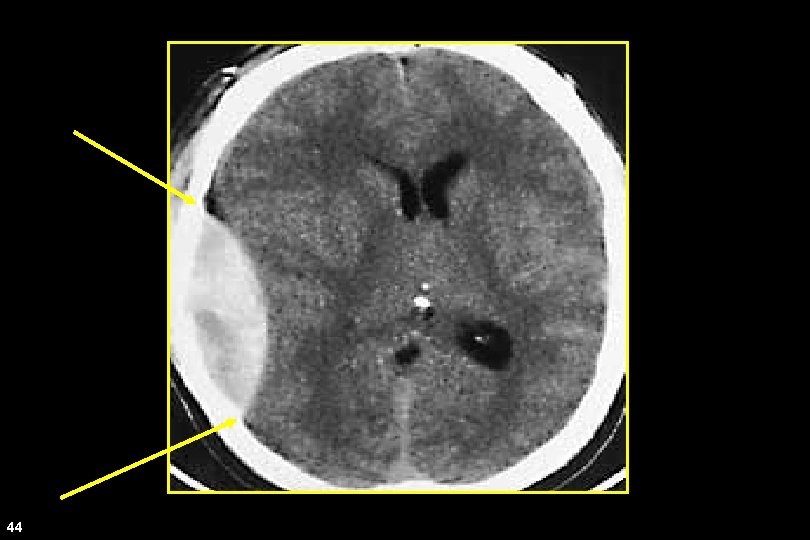

Epidural Hematoma • Lens shaped • Does not cross sutures • Classically described with injury to middle meningeal artery • Low mortality if treated prior to unconsciousness ( < 20%) 43 Andrew D. Perron, MD, FACEP

CT Scan 44